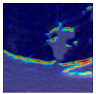

Experiment 3: Clinical Validation on Real-World CT Data

To assess clinical applicability, the model was validated on MEF-PN35—a real-world dataset comprising 804 CT slices from 35 patients with diverse nodule morphologies. Performance was evaluated using the Dice score, sensitivity, specificity, and Miss Rate. Additionally, Grad-CAM visualizations were employed to interpret attention consistency, offering qualitative insights into the model’s focus on lesion regions in realistic clinical scenarios.

To complement the quantitative evaluation, we present a set of representative cases from the clinical dataset that exhibited typical segmentation challenges. These cases were selected to reflect diverse morphological characteristics observed in pulmonary nodules, such as spiculated boundaries, small size, vessel adherence, pleural attachment, cavitation, and clear isolation. Rather than aiming for exhaustive categorization, our intent is to highlight a range of practical difficulties encountered in real-world scenarios and to qualitatively assess how different boundary-aware loss functions respond to these variations. Each challenge is labeled (C1) through (C5) in Table 10 and is consistently referenced in the corresponding detailed illustrations that follow.

Following the summary in Table 11, we present detailed visual comparisons for selected representative cases, each corresponding to a specific segmentation challenge. These cases are consistently labeled using the Challenge ID (CID) codes defined in Table 9 to facilitate cross-referencing between the summary and the case illustrations. Each table reports segmentation results across three loss configurations (Sobel, Laplacian, and Hausdorff) using five columns. Loss indicates the boundary loss formulation applied in each case, where Dice loss is combined with a boundary term computed using Sobel, Laplacian, or Hausdorff operators. The Segmentation Result column shows four images side by side: the input CT patch, the manual ground truth, the model prediction, and a color-coded difference map between ground truth and prediction. In this map, green indicates true positives, blue represents true negatives, red corresponds to false positives, and yellow denotes false negatives. The final column, Attention Map, presents Grad-CAM visualizations derived from one of the Adaptive Attention Fusion (AAF) layers in the encoder path. These maps illustrate the spatial focus of the model, with red/yellow regions indicating strong attention and lighter or neutral tones indicating lower activation. All six cases are presented in detail in Table 11, Table 12 and Table 13, providing a comprehensive qualitative analysis of how each loss configuration performs under specific segmentation challenges observed in real clinical data.